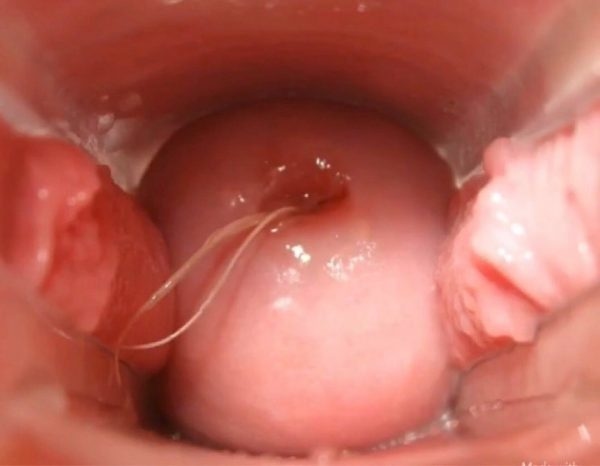

Viêm cổ tử cung là tình trạng viêm nhiễm ở cổ tử cung của nữ giới, gây tình trạng sưng tấy, mưng mủ hoặc xung huyết. Tác nhân chính gây bệnh là nấm, vi khuẩn xâm nhập và tấn công gây viêm.

Viêm cổ tử cung là tình trạng không hiếm gặp ở nữ giới